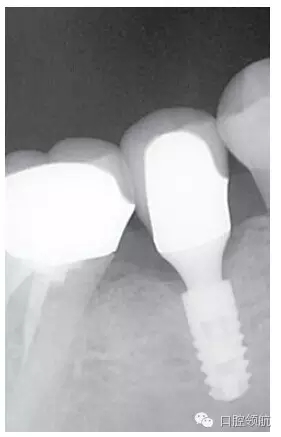

種植體的基臺與上部修復體的密合性,通過口腔X線片進行檢查,確認種植體周圍有殘留的粘接劑(圖2),使用探針等器械盡力清除剩余粘接劑,避免預后不良因素的產(chǎn)生。然后,通過X線片從投照的方向檢查確認剩余的粘接劑,完全沒有殘留粘接劑的實際狀態(tài)(圖3)。

圖3 大約經(jīng)過3年的觀察未發(fā)現(xiàn)大的改變,與預期想象的一樣穩(wěn)定。